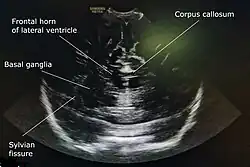

Cranial ultrasound is a technique for scanning the brain using high-frequency sound waves. It is used almost exclusively in babies because their fontanelle (the soft spot on the skull) provides an "acoustic window". A different form of ultrasound-based brain scanning, transcranial Doppler, can be used in any age group. This uses Doppler ultrasound to assess blood flow through the major arteries in the brain, and can scan through bone. It is not usual for this technique to be referred to simply as "cranial ultrasound". Additionally, cranial ultrasound can be used for intra-operative imaging in adults undergoing neurosurgery once the skull has been opened, for example to help identify the margins of a tumour.[1]

A 5 to 7.5 MHz probe is used to scan deeper structures in the brain. A 7 to 12 MHz probe is used for scanning superficial structures for detecting lesions between the brain and the skull, superior sagittal sinus thrombosis, cerebral oedema, and evaluating the structures of sulci and gyri.[4]

A water-based gel is applied to the infant's head, over the anterior fontanelle, to aid conduction of ultrasound waves. Ideally scans are performed during sleep or when the infant is calm. The operator then uses an ultrasound probe to examine the baby's brain, viewing the images on a computer screen and recording them as necessary.

A standard cranial ultrasound examination usually involves recording of approximately 11 views of the brain from different angles, six in the coronal plane and five in the sagittal and parasaggital planes.[7] This allows all parts of the ventricles and most of the rest of the brain to be visualised.